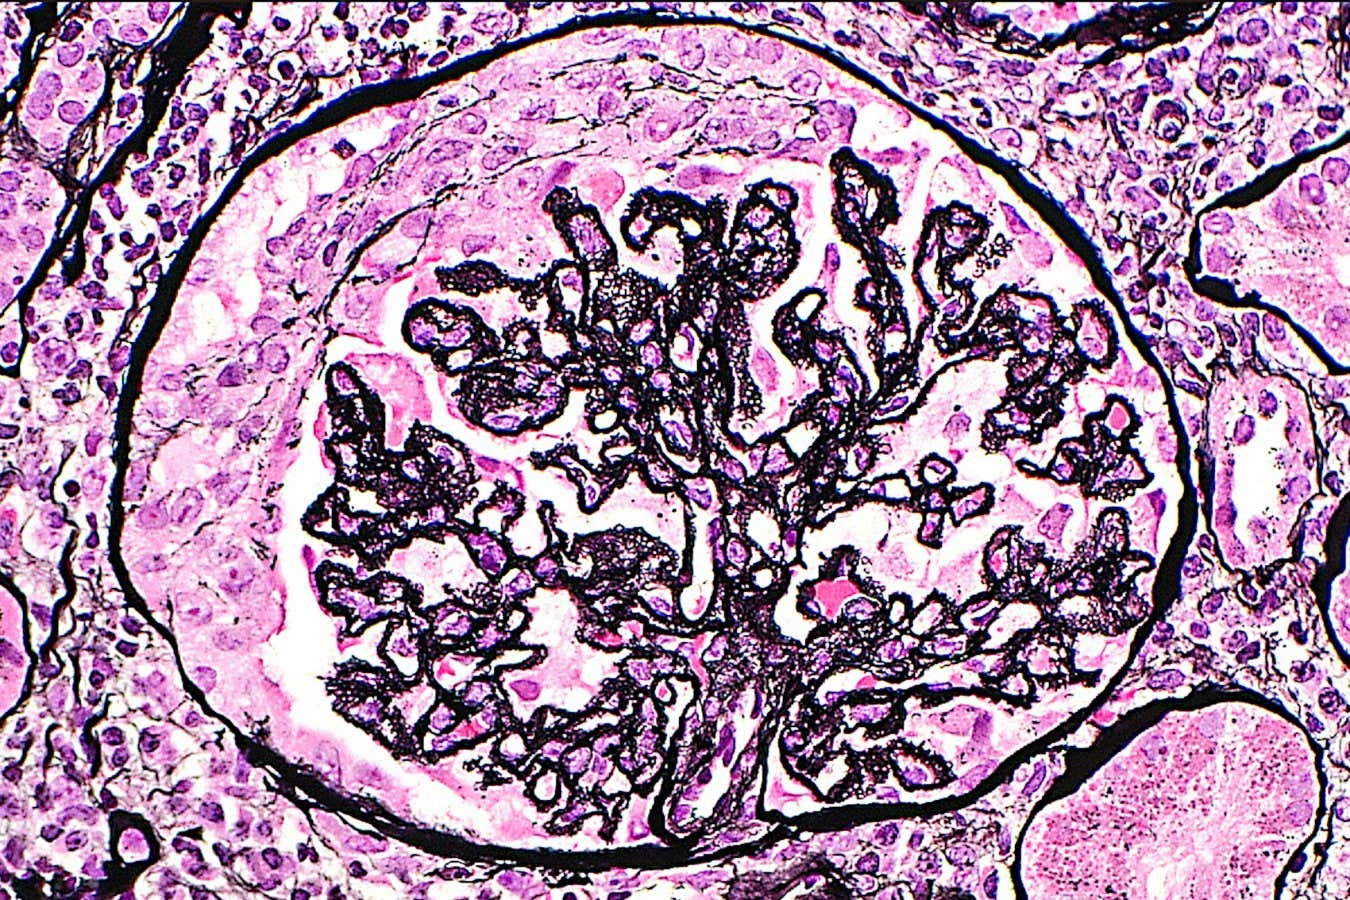

Autoimmune conditions like lupus can be mistaken for perimenopause

ZIAD M. EL-ZAATARI/SCIENCE PHOTO LIBRARY